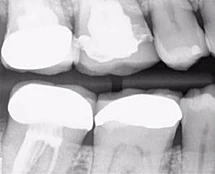

Mẹ tôi có tiền sử chấn thương khi đang chơi tennis với bố vài năm trước đây. Trước đó khi khám ở bác sĩ tổng quát, phim cận chóp hàm dưới gợi ý phải điều trị tủy, bà đến chỗ tôi ngay lập tức. Chất lượng phim cận chóp của chỗ bác sĩ trước không giống của mình, do đó tôi chụp lại một phim khác (Hình 17). Không chỉ thấy tổn thương nội tiêu nhỏ ở răng 46 mà còn tổn thương tiêu mở rộng răng 31 và 41 ban đầu khiến tôi nghĩ răng này không còn hy vọng gì và phải nhổ đi làm implant.

Hình 17: Ảnh XQ trước điều trị

Tuy nhiên sau khi chụp 3D, tôi đã có thể thấy mức độ tiêu xương ở lát cắt ngang, đứng dọc, đứng ngang; điều may mắn là nó không vượt ra khỏi phạm vi răng (hình 18 và 19).